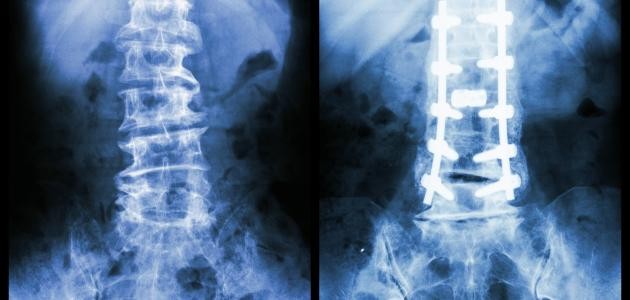

• إرجاع اجزاء العظم الى الوضع المقبول طبيا وتكون عملية الإرجاع اما بطرق مغلقة اوعن طريق تداخل جراحي

• تثبيت اجزاءالعظم في الوضع المقبول طبيا لحين التئام العظم وتكون عمليةالتثبيت اما عن طريق الجبائراوالمثبتات او اثقال متصلة بالطرف المصاب او عن طريق اجراء تداخل جراحي وتثبيت الكسر بواسطة الأسياخ او الصفائح المعدنية و خلال هذه الفترة يتم

التأهيل الطبيعي لمساعدة المصاب فيعودته لأداء وظيفته.